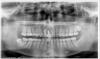

taurus1010 Опубликовано 20 сентября, 2012 Поделиться Опубликовано 20 сентября, 2012 Уважаемые хирурги!Хотел бы узнать ваше авторитетное мнение по моему случаю.1. Детская травма - выбили 11-ый зуб в 10-летнем возрасте.2. Через 15 лет почувствовал давление в области. Сфотографировал -- киста над 11,12. (См. снимок "2003 г").3. с 2003 по 2007 было произведено четыре резекции верхушек корней без подсадки костного материала. Четыре, т.к. были свищи, болевые ощущения, недомогание.4. После последней резекции с 2007-2008 года состояние стабилизировалось. Не беспокоило. (См. снимок "дек 2010_контрольный")5. В августе 2012 происходит продольный перелом 12 зуба (жесточайше кусанул замерзшую в камень изюмину в мороженом, блин...). Обломок лицевой части коронки уходит на 3 мм. под десну. (См. цветные фото)6.Предложено: а)удаление 12, 11 зубов, чистка кистозной зоны и одномоментная имплантация (+подсадка синт.костного материала от Альфа Био) с немедленным временным протезированием на временных абатментах с выведением коронок из прикуса и шинированием конструкции на период остеоинтеграции посредством объединения временных коронок между собой. б)Также есть предложение классическое: удаление 11,12-->аутокостная пластика с мембраной+ бабочка--> 3 месяца-->контроль-->имплантация+ бабочка--> 6 мес.--->контроль--> постоянное протезирование безметалловой керамикой. Вопрос:1.Какой план лечения по вашему мнению будет оптимальным с учетом эстетически важной зоны?(Классическая: аутокостная пластика+бабочка+отсроченная имплантация ч/з 3 мес.либо одномоментная имплантация + бабочка, либо одномоментная имплантация + временные коронки)2. Показана ли мне немедленная имплантация после удаления зубов с учетом истории болезни (хронический процесс)?3. Возможно ли при одномоментной имплантации провести кюретаж с высокой эффективностью, чтобы возможная инфекция не привела в отдаленной перспективе к потере имплантата?4. Сравнимы ли будут отдаленные результаты немедленной и классич.имплантации в моем случае?5. Бабочка. Испортит ли она мне междесневые сосочки? Есть противоположные мнения. Благодарю. Ссылка на комментарий